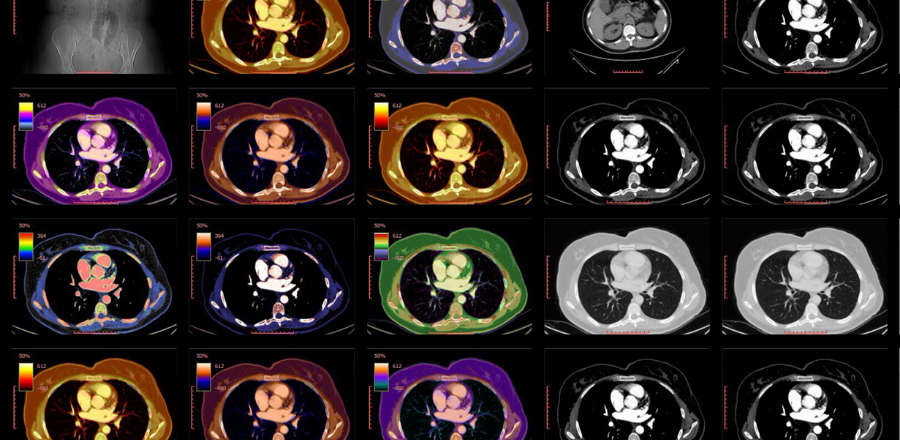

The AMA has been discussing the ongoing shortages of iodinated contrast media (contrast) with the TGA. The shortage has been caused by COVID-19 lockdowns in Shanghai.

TGA statement: Shortage of iodinated contrast media (contrast) diagnostic agents

RANZCR statement: RANZCR Statement on Iodinated Contrast Media Shortage